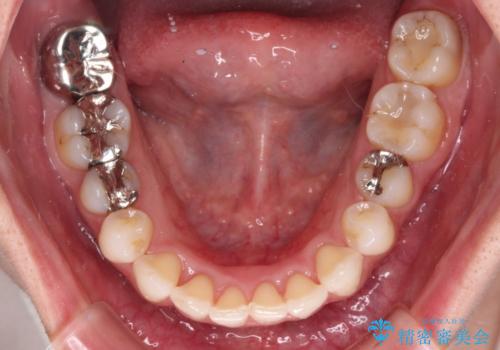

- 上下の前歯のデコボコを治したいとのことで来院された患者様です。

上下顎ともにIPR(歯と歯の間を削る)と歯列全体の拡大によって叢生が解消するように設計し、インビザラインにより治療を行うこととしました。

1日22時間の装着時間を守ってくださったので、比較的早く治療を終える予定でしたが、各国での入国制限が厳しくなり、帰国のタイミングに合わせてのんびりと治療を進めることとなってしまい、やや長期間の治療となりました。